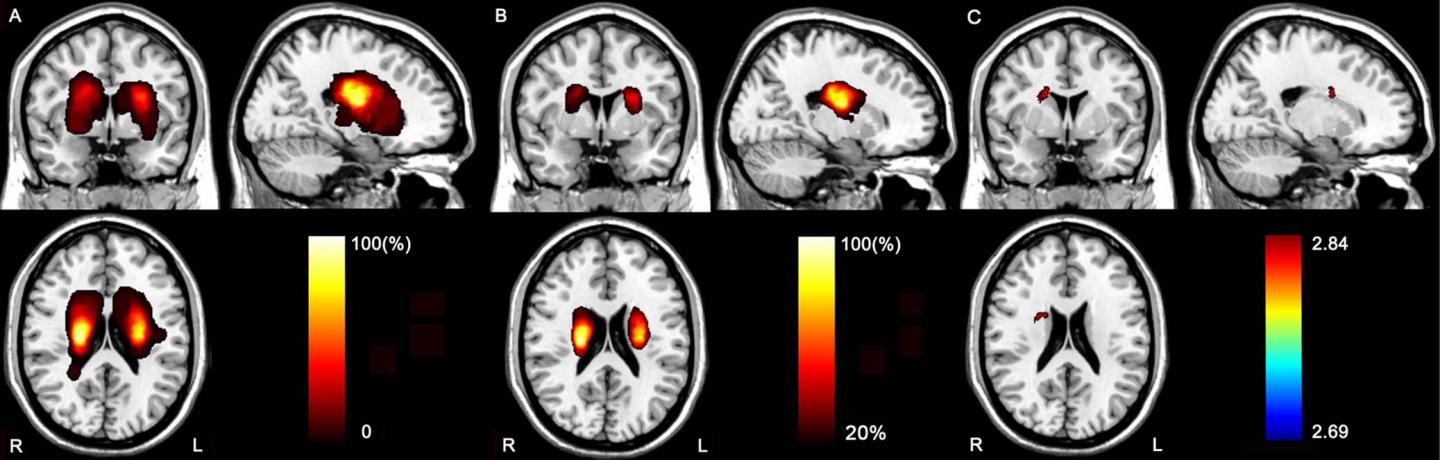

image: Stroke lesions. A, Lesion incidence map in patients with acute stroke. B, Lesion incidence map shows regions in which at least 10 patients had a lesion. Color bar denotes the probability of lesion distribution. C, Brain region that is correlated with attention deficit in the voxel-based lesion-symptom mapping (VLSM) analysis. Color bar denotes the t values.

To investigate the mechanisms underlying attention deficit in chronic subcortical stroke, Dr. Yu and colleagues combined voxel-based lesion-symptom mapping (VLSM) and diffusion tensor tractography (DTT) in 49 patients (32 men and 17 women between the ages of 40 and 71) after subcortical stroke and 52 control patients (30 men and 22 women, age 40-68). VLSM is a method of analyzing relationships between tissue damage and behavioral deficits, and DTT is an MRI technique that allows for 3-D visualization of specific white matter tracts in the brain.

A modified version of the attention network test was used to assess visual attention function. VLSM was used to identify lesion locations related to attention deficit in the stroke patients. Then DTT was used to determine the responsible impaired brain connections at the chronic stage (> 6 months post-stroke).

The results showed that compared to the controls, patients with chronic stroke exhibited prolonged reaction time during the attention task. VLSM revealed that having an acute stroke lesion in the right caudate nucleus and nearby white matter was correlated to the prolonged reaction time. DTT showed that the responsible lesion was located in the right thalamic- and caudate-prefrontal pathways in controls.